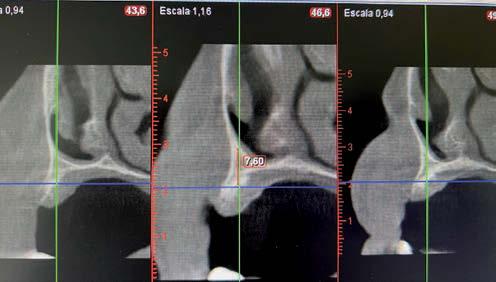

técnicas de abordaje de seno maxilar: elevación convencional o la inserción de implantes cortos y extra-cortos mediante elevación transcrestal, desde enero de 2010 en adelante. Todos los pacientes fueron estudiados antes de la inserción de los implantes mediante modelos diagnósticos, exploración intraoral y realización de un TAC dental (Conebeam) analizado posteriormente mediante un software específico (BTI-Scan II).